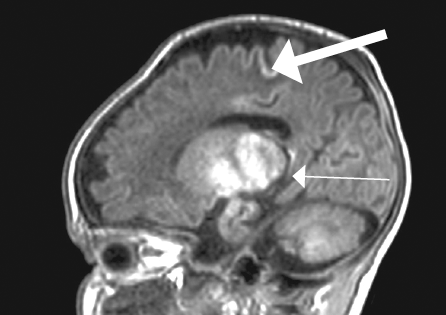

Краниальную сонографию выполняли в динамике. При выполнении КСГ в последующие месяцы отмечалось нарастание атрофических изменений головного мозга — расширение субарахноидальных пространств (до 15 мм), истончение кортикальной пластины, расширение пространств между бороздами и извилинами, расширение боковых (передних и центральных отделов) и третьего желудочков мозга (рис. 3).

Рис. 3. Краниальная сонография пациента. Фронтальный скан в В-режиме / Fig. 3. Cranial ultrasound. Frontal scanner B-image

Визуализируется смешанная гидроцефалия по атрофическому типу (расширение субарахноидальных пространств, межполушарной щели, передних отделов боковых желудочков), истончение корковой пластины, расширение межбороздного пространства.